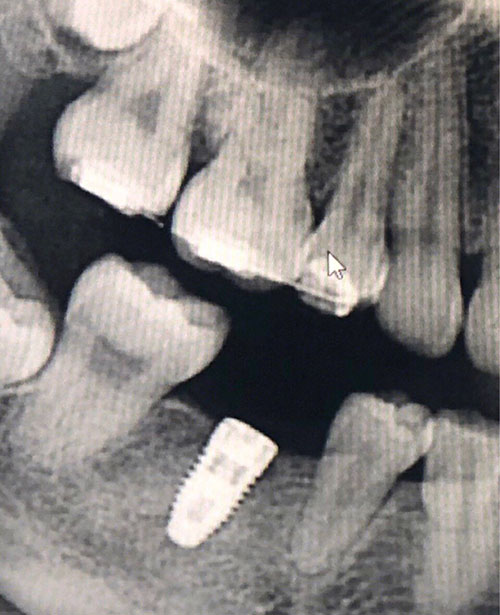

種植牙牙片